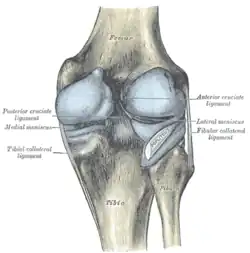

La rodilla está sustentada por fuertes ligamentos que impiden que sufra una luxación, siendo los más importantes el ligamento lateral externo, el ligamento lateral interno, el ligamento cruzado anterior y el ligamento cruzado posterior.[4]

Ligamentos

La rodilla esta sustentada por varios ligamentos que le dan estabilidad y evitan movimientos excesivos. Los ligamentos que están en el interior de la cápsula articular se llaman intraarticulares o intracapsulares, entre los que se encuentra el ligamento cruzado anterior y el ligamento cruzado posterior. Por otra parte los ligamentos que están por fuera de la cápsula articular se llaman extrarticulares o extracapsulares como el ligamento lateral interno y el ligamento lateral externo.[8][9]

Intraarticulares

- Ligamento cruzado anterior (LCA).

- Ligamento cruzado posterior (LCP).

- Ligamento yugal o ligamento transverso. Une los meniscos por su lado anterior.

- Ligamento meniscofemoral anterior o Ligamento de Humphrey. Del menisco externo al cóndilo interno del fémur.[10]

- Ligamento meniscofemoral posterior o Ligamento de Wrisberg. Del menisco externo al cóndilo interno del fémur, por detrás del meniscofemoral anterior.[11]